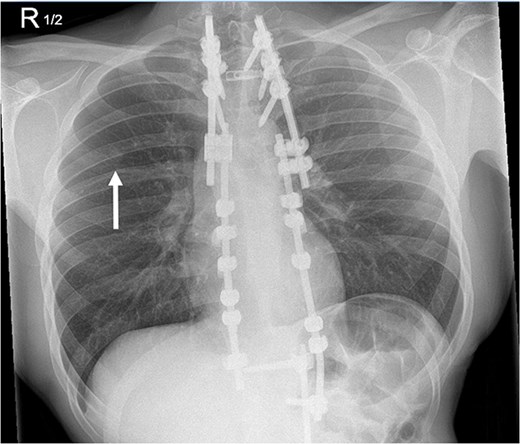

Subsequent computed tomography (CT) scan and positron emission tomography (PET) scan (Figs 2 and 3) confirmed the presence of three nodules in the right lung, suspicious for sarcoma metastases. An anterior, pleural-based upper lobe lesion, a posterior lower lobe lesion, and a lesion located at the bifurcation of his right middle and lower lobes.

Transverse and saggital views of the three nodules identified on an investigative CT scan.

The pleural-based anterior right lobe lesion showed fluorodeoxyglucose uptake on a PET scan.